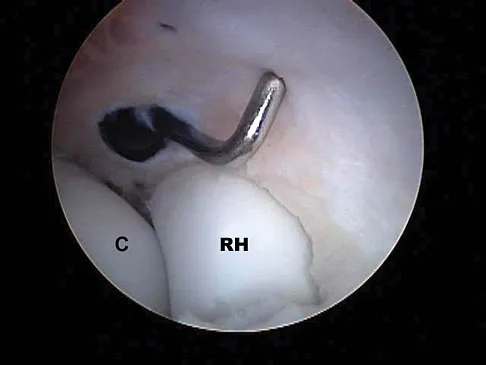

A 28-year-old man sustained a shoulder dislocation 2 years ago. It remained dislocated for 3 weeks and required an open reduction. He now reports constant pain and has only 60 degrees of forward elevation and 10 degrees of external rotation. He desires to return to some sporting activities. An AP radiograph and intraoperative photograph (a view of the humeral head through a deltopectoral approach) are shown in Figures 31a and 31b. What is the best treatment option to decrease pain and improve function?

Explanation